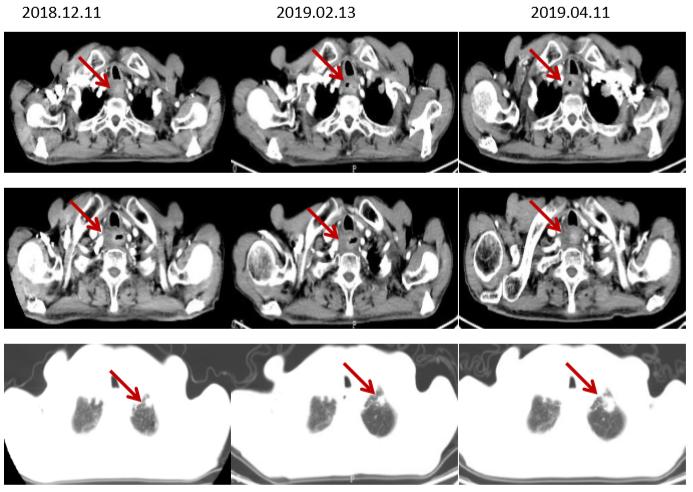

2018.06入院复查疾病进展(食管上段占位,较前相仿;双肺多发结节,较前增大、增多,考虑转移),病理补做免疫组化:PDL-1 (5%弱+)。筛选入组“在一线治疗失败的晚期/转移性食管鳞癌受试者中比较IBI308与紫杉醇或伊立替康治疗有效性和安全性的随机、开放、多中心、II期研究(ORIENT-2)”的临床试验。入IBI308组,于2018.06.27、2018-7-17、2018-08-09、2018-8-31、2018-9-20、2018-10-11、2018-11-01、 2018-11-22、 2018-12-13、2019-01-03、2019-01-22给予“IBI308”治疗13周期。

2周期复查(2018.08.07)部分肺转移灶较前稍增大(假性进展),4周期及以后食管壁增厚较前好转,肺转移灶较前缩小,临床疗效PR。

CT(脑转移治疗前后食管病灶及肺转移灶对比,部分肺转移灶较前增大)

CT(食管增厚较前明显改善,肺转移灶较前缩小)